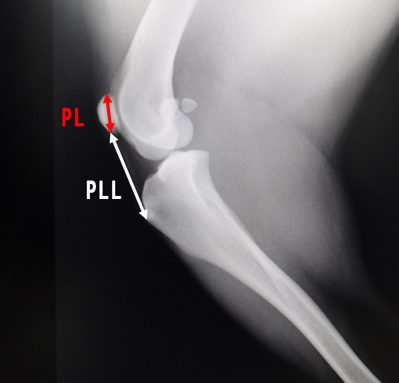

膝蓋高位症(パテラアルタ)について

膝蓋骨が高い位置にある場合にX線検査による測定式が存在する。

- 膝蓋骨の長さ(PL)

- 膝蓋靭帯の長さ(PLL)

- PLL/PL比の計算をする、PLL/PL>1.97

- 犬 (小型犬)

正常・・1.7(平均)

MPL・・1.87 (平均)

Alta・・1.87(平均)

参考程度:中・大型犬では2.06以上は内方脱臼のリスクが増加